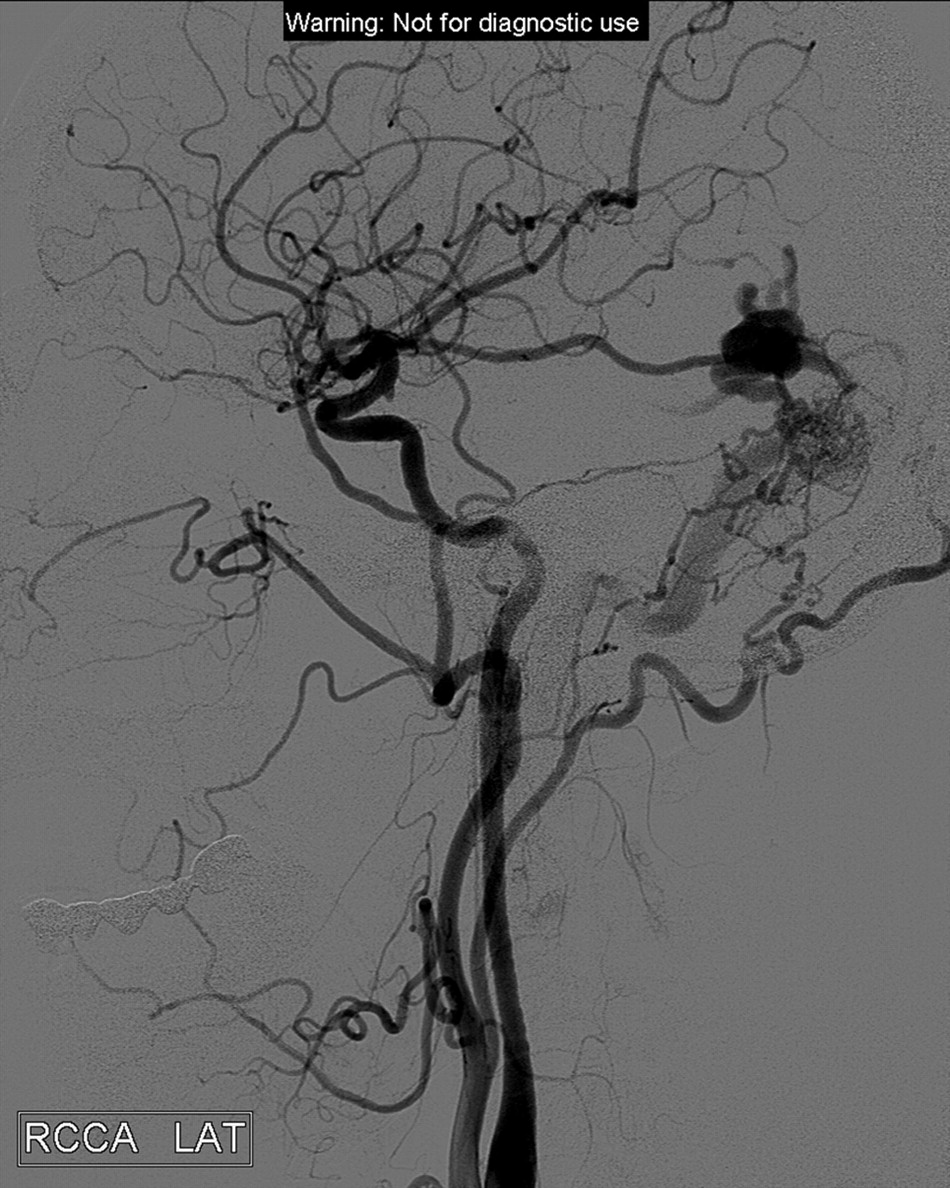

Left lateral common carotid artery. A DAVF fed mainly by middle meningeal branches draining to cortical veins with a varix.

A, Superselective injection with the Sonic microcatheter. Image demonstrates the fistula and the pial cortical draining vein with the varix, draining to the vein of Labbe. B, The final cast includes the proximal part of draining vein and the network of feeders. C, The completion injection and full closure of the fistula.